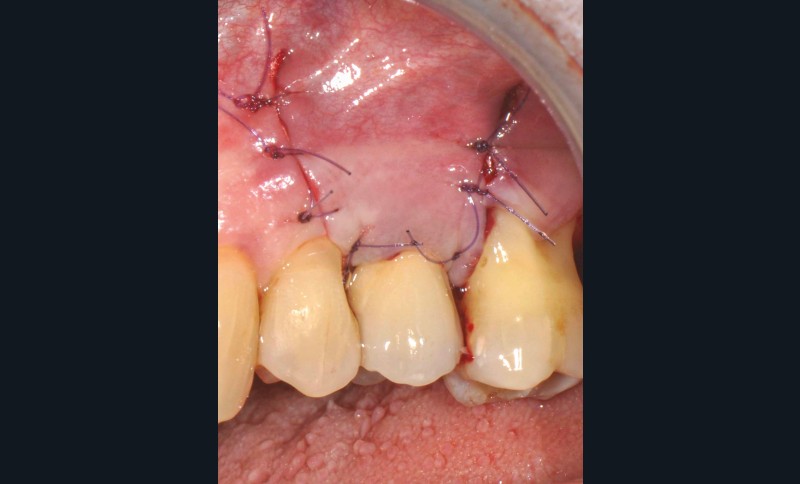

13 et 14. À 3 ans, une régénération osseuse satisfaisante et un bel aspect des tissus péri-implantaires sont observés. Les poches font 3 mm en mésial, distal et palatin, et 2 mm en vestibulaire. Il n’y a pas de saignement au sondage.